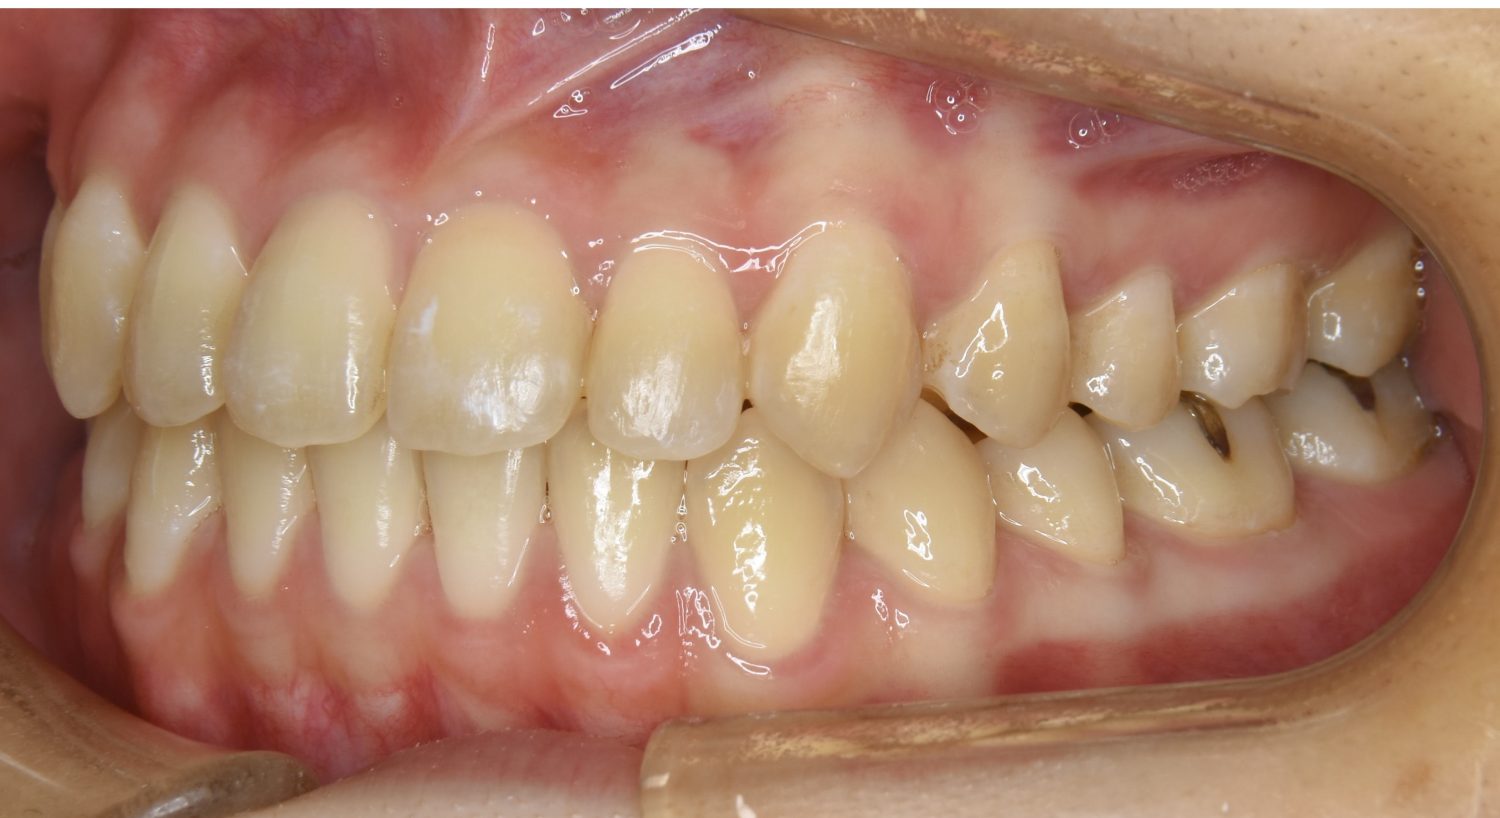

前歯部開咬の症例紹介②

After

主訴

前歯で物が噛めない

治療内容

上下ラビアルブラケット(唇側装置)に矯正用アンカースクリューを併用し非抜歯で治療を行いました。

上下の前歯が開いており前歯では全く噛めていない状態でした。臼歯の圧下を行うことで機能面のみでなく審美面も改善しました。